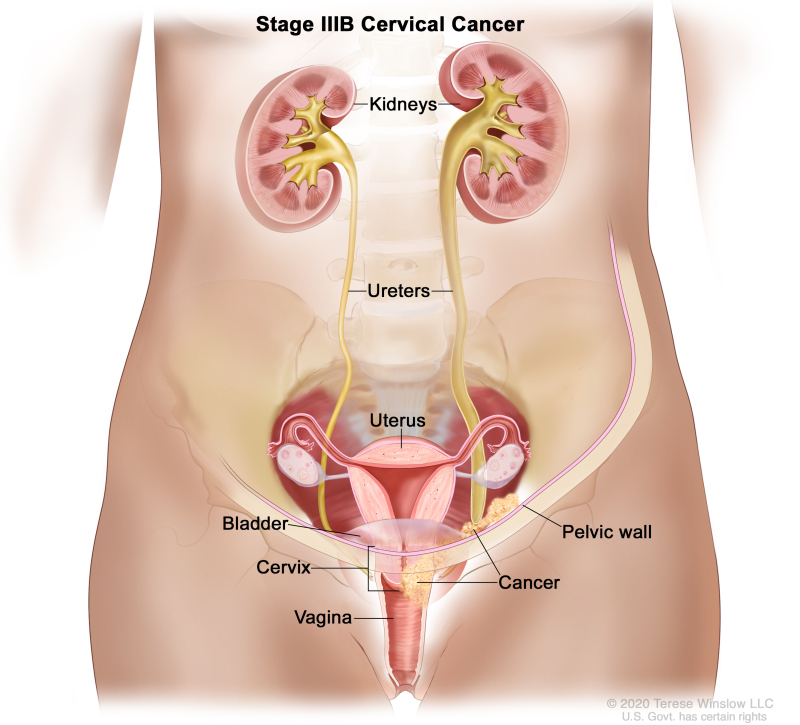

You may strengthen the body's immune system and quite simply create resistance to an hpv infection in basically just a few months, prior to the time that it could originate any important. Ad all cervical cancer treatments are not the same is what you've tried not working? Learn about the stages of cervical cancer and what they mean.

Treatment options include radiation therapy with or without chemo to try to slow the growth of the cancer or help relieve symptoms. Foods high in vitamin c, selenium, carotenoids, and vitamin e. Most standard chemo regimens include a.